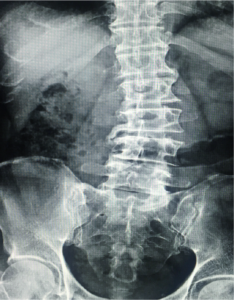

Fracture of The lumbar spine

The backbone is made of small bones arranged from the neck region down to the buttocks, one above the other. The region at the chest…

Fracture Of The Thoracic And Lumbar Spine